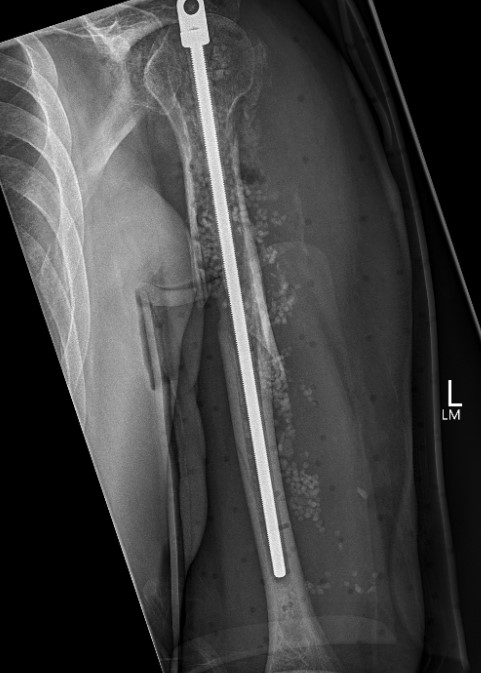

Humeral Fracture SegmentalHumeral Plate LateralHumeral Plate Long AP

Segmental fracture ORIF